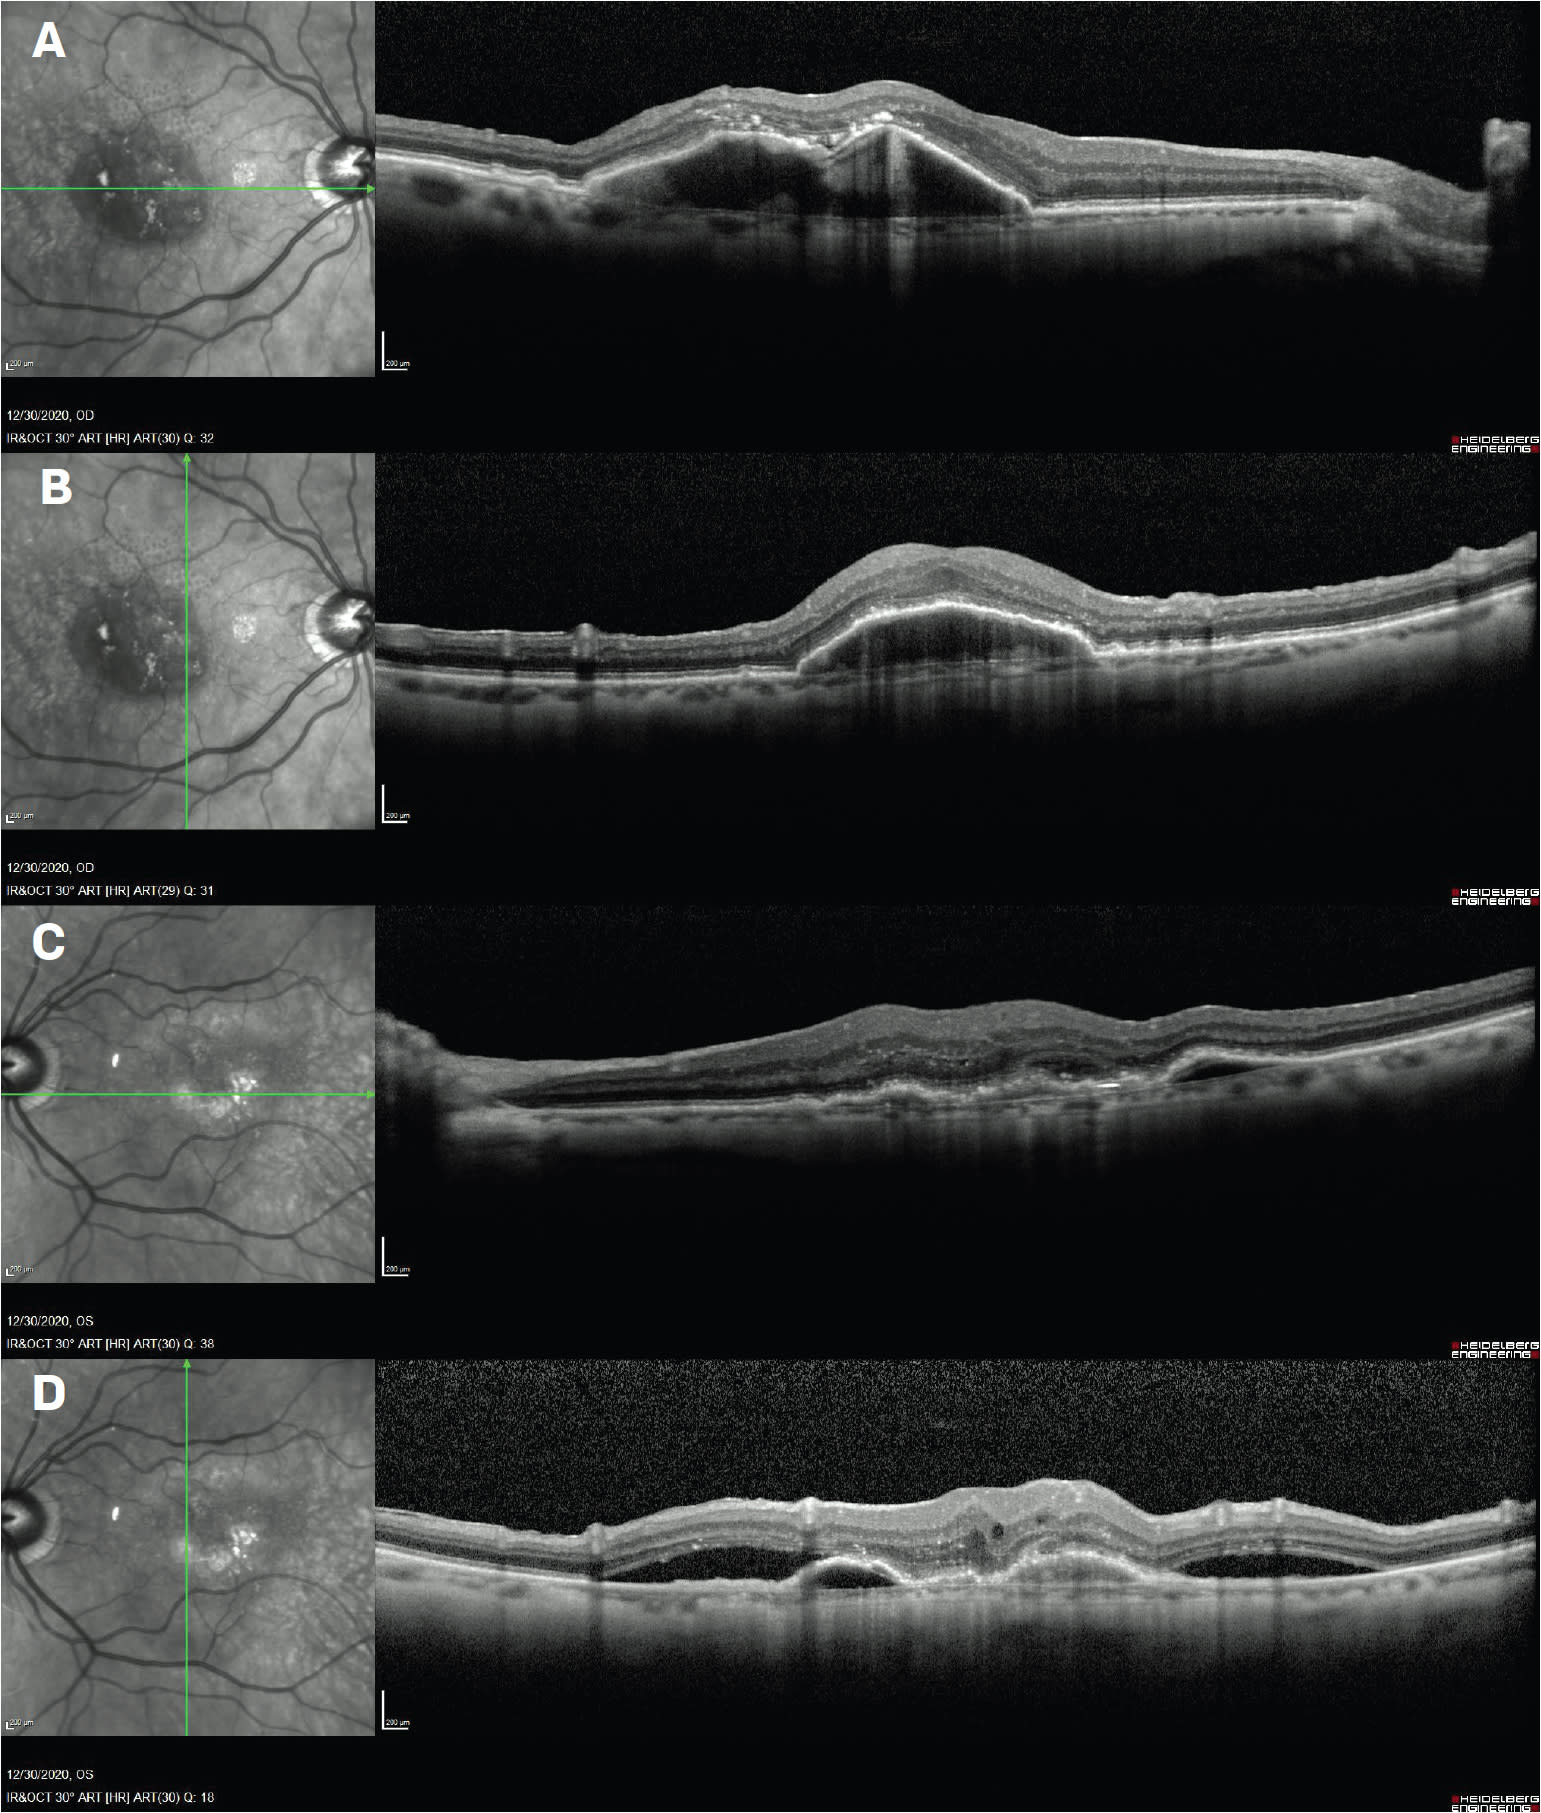

Jan 27, 2021: Upon return to the clinic, the patient reports that: “My vision in the left eye is much better.” Acuity is now 20/40- OD and 20/50 OS. There is essentially unchanged stable anatomy OD, consistent with the patient’s reports of stability with regular aflibercept injection, and improved anatomy with a reduction of PED, essentially resolved SRF, and organization of the retina OS (Figure 2). The patient elects to proceed with brolucizumab injection OU. ◆